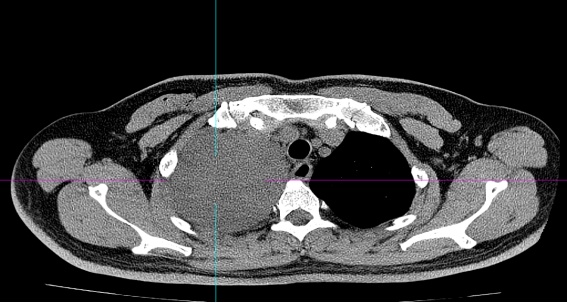

患者黄某因近3个月来反复咳嗽、久治不愈,前往当地医院就诊。检查结果让他和家人大吃一惊:右侧胸腔内竟长有一个巨大的肿块。胸部增强CT显示肿块大小约16cm×12cm,且与胸膜顶大血管关系极为密切。

手术前一天,胸部肿瘤外科牵头组织了由放射科、麻醉科、手术室、病理科、胸部肿瘤内科组成的多学科团队(MDT)进行全院大会诊。专家们通过三维重建技术对患者的影像资料进行精确评估,精准锁定肿瘤与血管及重要脏器的解剖关系,并针对手术中可能出现的三大难点制定了周密预案:

2. 避免损伤血管及周围脏器:仔细研判肿瘤与胸膜顶的粘连程度,力求在完整切除肿瘤的同时,避免损伤血管右无名静脉及右锁骨下动静脉,最大限度保留正常生理功能。